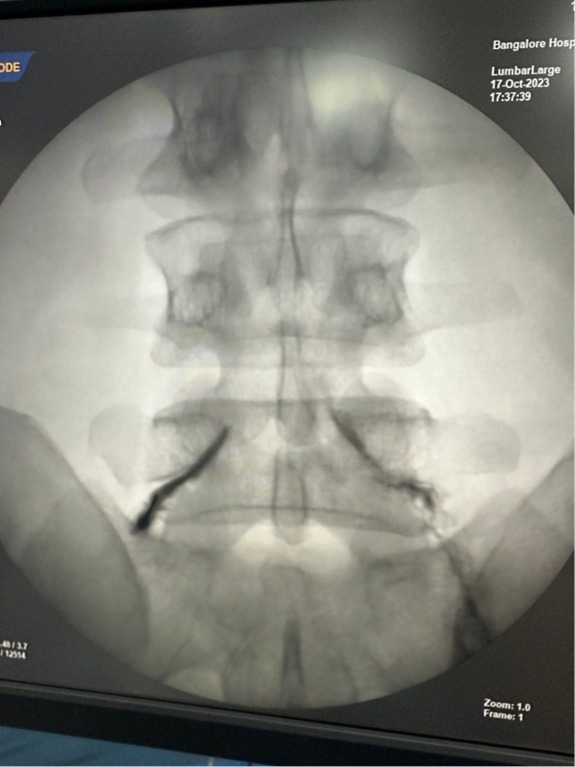

All procedures are done under sterile, image-guided conditions — usually in a day-care setting. Using C-arm fluoroscopy, ultrasound, or navigation systems, I deliver medication or radiofrequency energy directly to the pain generator with millimeter precision. Most patients go home within a few hours.

Before & After Clinical Gallery

We showcase real patient cases (with consent), including:

- Pre- and Post-operative MRIs and X-rays

- Disc Herniations, Stenosis, and Spondylolisthesis cases

- Visible improvement in alignment and decompression